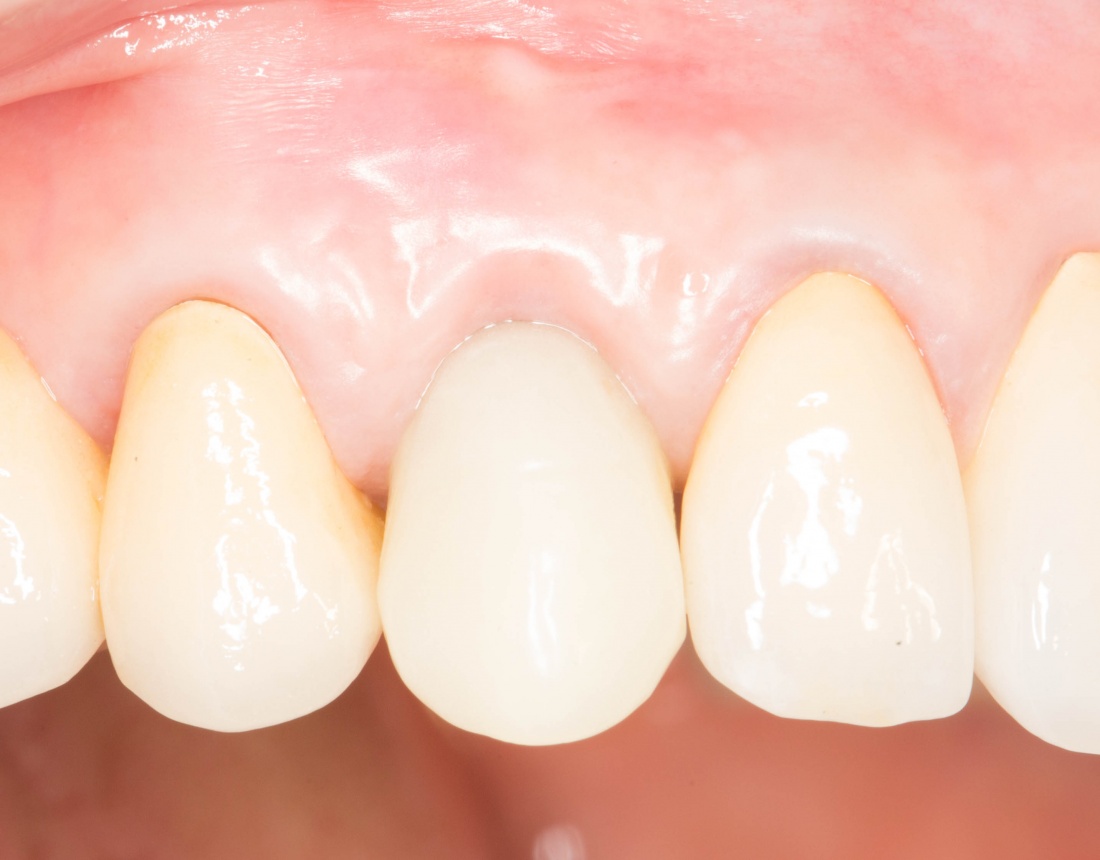

Рекомендации по установке имплантов. Для всех. Часть V.